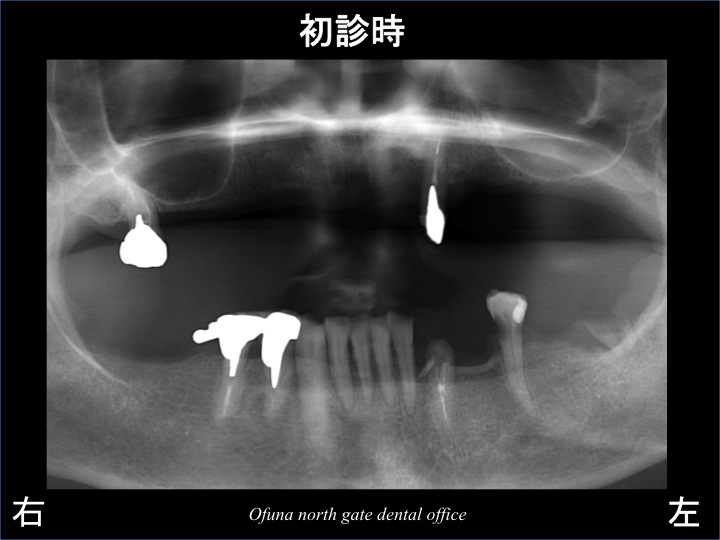

患者様は、初診時 上顎に2歯しか歯が存在しない方でした。

早速初診時のレントゲンを見てみましょう。

上顎は、右の奥歯 と 左の前歯 だけが残っている状態でした。

この2歯に入れ歯の金具がかかっており、義歯を安定させていました。

しかし、上顎左側の前歯がグラグラしてきたため、来院されました。

診査の結果、この歯は歯根破折 していました。

歯根破折しているため、抜歯と診断しました。